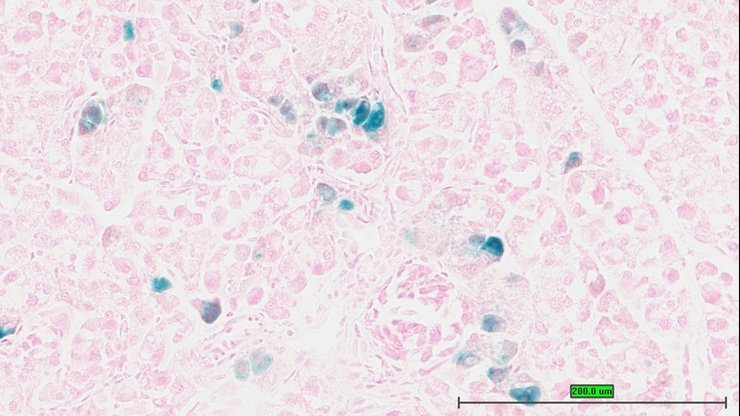

TS28: pancreas Present UC Davis_1851002

TS28: pancreas Present UC Davis_1851003

TS28: pancreas Present UC Davis_1851004

TS28: pancreas Present UC Davis_1851005

TS28: pancreas Present UC Davis_1851006

TS28: pancreas Present UC Davis_1850990

TS28: pancreas Present UC Davis_1850991

TS28: pancreas Present UC Davis_1850992

TS28: pancreas Present UC Davis_1851021

TS28: pancreas Present UC Davis_1851022

TS28: pancreas Present UC Davis_1851023

TS28: pancreas Present UC Davis_1851024

TS28: pancreas Present UC Davis_1851025

TS28: pancreas Present UC Davis_1851026

TS28: pancreas Present UC Davis_1851044